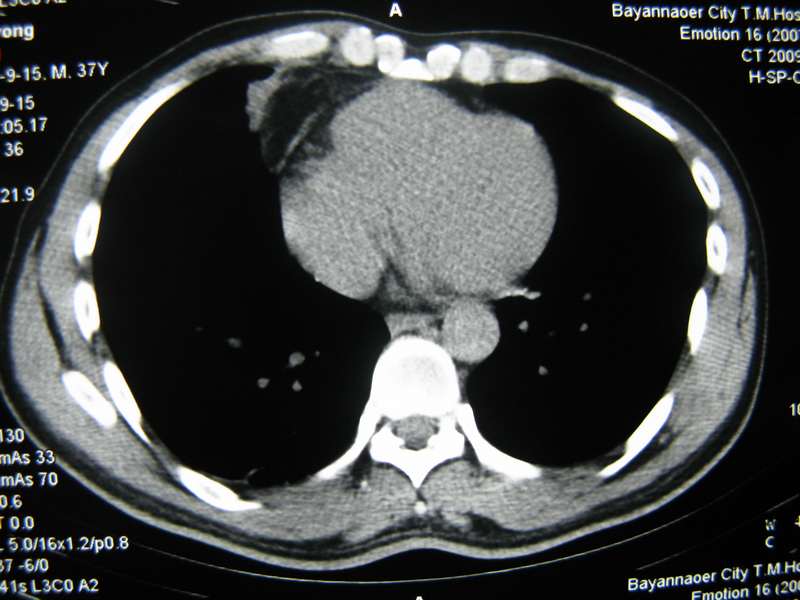

男,37岁,主述胸疼厉害,无咳嗽,无发热,血象也不高,病灶内ct值脂肪密度,右侧胸腔内少量积液,同道们考虑什么?谢谢!

两肺下叶基底段纤维灶,右肺下叶基底背侧相应胸膜肥厚,右肺中叶内侧段部分不张。前中下纵隔团块状脂肪影,随访除外胸腺脂肪瘤。